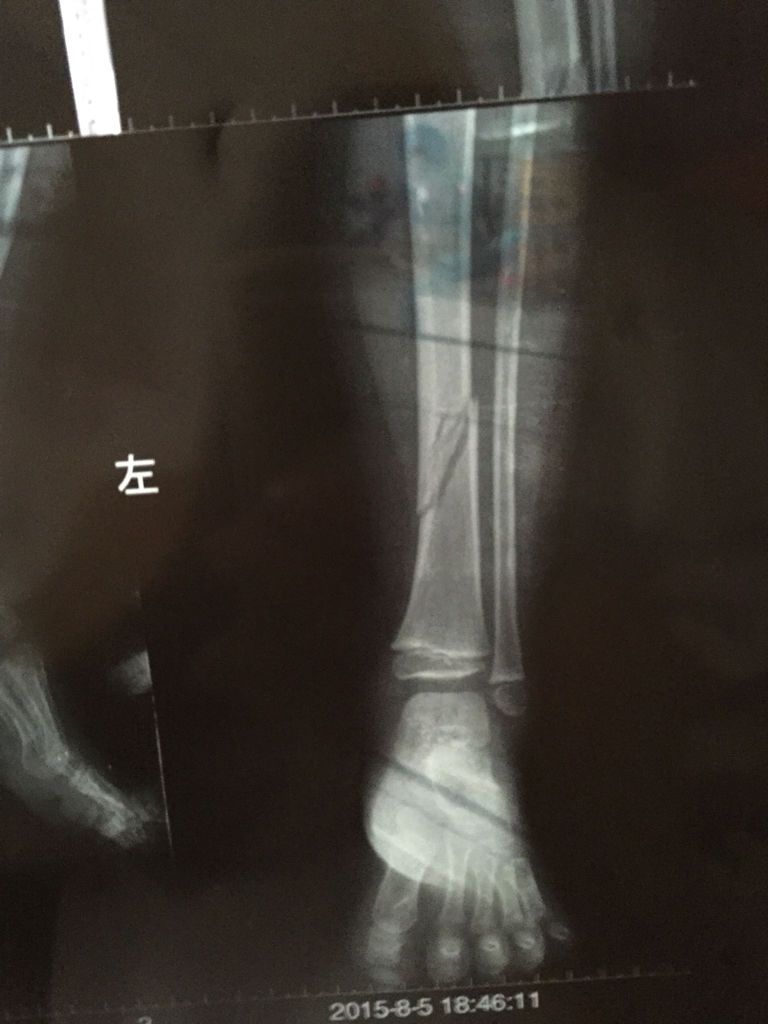

3岁小孩左侧胫骨下1/3段骨质断离,骨皮质连续性中断 点击展开 匿名用户 2015-08-12 17:13 满意回答 由于骨折,需要做内固定或是外固定治疗,可以渐挡服降毯用些促进骨生长的药敲法苦物。 longtou543306 2015-08-12 17:14 宝宝知道提示您:回答为网友贡献,仅供参考。 相关问题 孩子10岁,CT显示左胫骨下段内侧局部骨皮质内见局限性骨质 你好羊胫骨治疗骨质增生方可行吗 磁共振检查记录:双膝关节对位好 股骨,胫骨骨质完整…